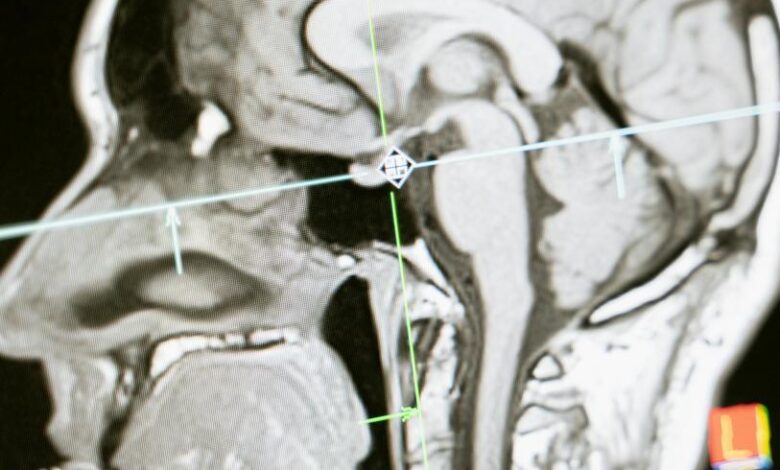

El infarto cerebral ocurre cuando un coágulo bloquea una arteria del cerebro, impidiendo el paso de la sangre hacia zonas clave. Esto provoca la pérdida de funciones como el habla o el movimiento.

“La arteria se tapa, deja de llevar la sangre a una zona y el paciente pierde la función de esa parte del cerebro”, explicó la médico internista y neuróloga Vanessa Cano durante una conferencia organizada por Boehringer Ingelheim.

¿Cómo actúa el fármaco en el cerebro?

Los trombolíticos, como la tenecteplasa, actúan directamente sobre el coágulo que bloquea la arteria. Su función es desintegrarlo para permitir que la sangre vuelva a fluir.

“El medicamento va directamente al coágulo, rompe sus uniones y permite que la sangre vuelva a pasar”, detalló Cano.

Este proceso puede ayudar a recuperar funciones neurológicas si se aplica dentro de una ventana de tiempo segura, generalmente dentro de las primeras 4.5 horas tras el inicio de los síntomas.